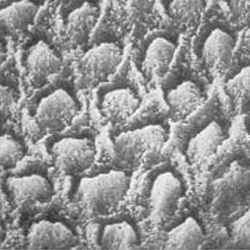

Para hacer la explicación más sencilla, os dejamos más adelante imágenes de la estructura del tejido más resistente que tenemos en el cuerpo humano, el esmalte. Por ser una de las estructuras más duras, precisamente es la que necesita un protocolo de grabado ácido para lograr la desmineralización y por tanto, la adhesión.

Gwinett J and Matsui A. Arch Oral Biol 1967; 12: 1615-9.